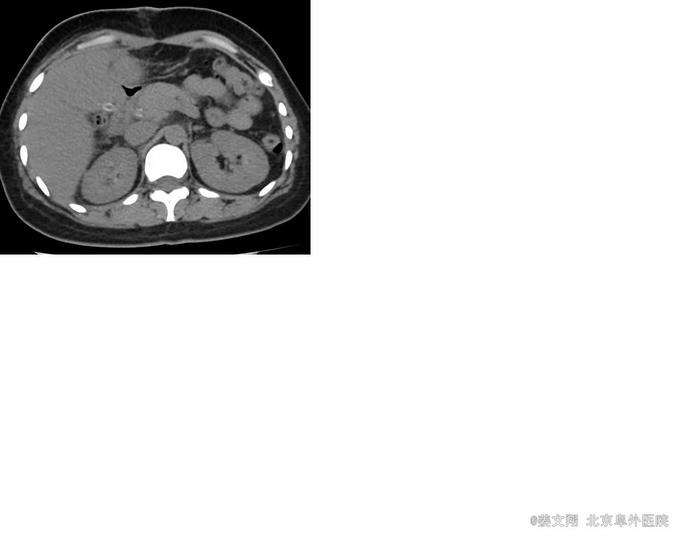

女,41岁,主诉:腹痛、呕吐伴发热1天。 现病史:患者1月前因反复发热2周伴腹痛入院,行腹部CT示:肝内胆管结石。完善检查后于2015-08-10行(腹腔镜中转开腹)肝左外叶切除、胆囊切除、胆总管切开取石、胆道镜探查取石、T管引流术。术后复查腹部CT提示:肝右叶胆管结石。患者术后恢复良好,带T管出院。1天前患者出现发热、右上腹部疼痛,呈持续性,痛疼向腰背部放射,伴恶心,呕吐数次,呕吐物为胃内容物,有寒战,为进一步明确诊断,积极、合理治疗,来中日医院普外科就诊,今收治入院。